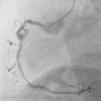

Homem, de 63 anos, recorre ao serviço de urgência do hospital mais próximo do local de férias por indisposição generalizada e dor mandibular com quatro horas de evolução, sendo diagnosticado enfarte agudo do miocárdio (EAM) da parede inferior. Já tinha antecedentes de EAM há quatro anos, em França, tendo colocado stents na coronária direita e circunflexa. Dado ser um centro sem capacidade de angioplastia, realizou fibrinólise nos primeiros 30 minutos, sendo depois transferido para centro com a mesma valência. A coronariografia revelou volumoso aneurisma no segmento médio da coronária direita em relação com porção proximal de stent, com trombo recanalizado (Figura 1). Foi tentada angioplastia para exclusão de aneurisma, mas não foi possível atravessar o stent com os fios guia utilizados. Ficou a ideia que a porção proximal do stent estaria ocluída, fazendo‐se o fluxo através da malha lateral. Dias depois fez‐se nova tentativa de angioplastia, apresentando aspeto de trombo organizado (Figura 2). Cruzou‐se a malha lateral do stent, mas não foi possível progredir um balão (Figura 3). A Figura 4 evidencia o resultado final.

Neste caso, destaca‐se a atempada fibrinólise, que mostrou ser a terapêutica ideal para o doente. As dimensões do aneurisma excedem em quatro vezes o calibre do vaso de referência, definindo aneurisma gigante. O bom fluxo, a incapacidade de resolução percutânea e a incerteza de evolução levantam o problema da necessidade ou do timing correto para correção cirúrgica. O doente teve alta sob dupla antiagregação e, após seis meses de follow up clínico, permaneceu sem eventos.